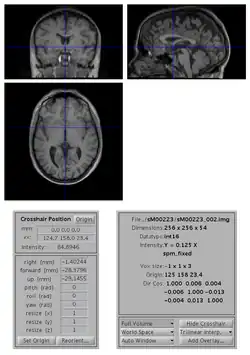

SPM Display

To change the origin of an image:

• open the image with SPM Display

• move the crosshair position so that it roughly points to the anterior commissure (AC).

• click on the Set Origin button

• click on the Reorient button and press done (your image is already selected). If you want to apply the same transformation to other images (e.g. if you have a series of functional images), select them all at this stage.

• say No to Do you want to save the reorientation matrix?

This will set the origin of the image (0 0 0 mm coordinates) to AC. You might also want to rotate the image such that it is better aligned with MNI space: to do so, you also need to edit the entries for the rotations (in radian) along the pitch, roll and yaw axes.